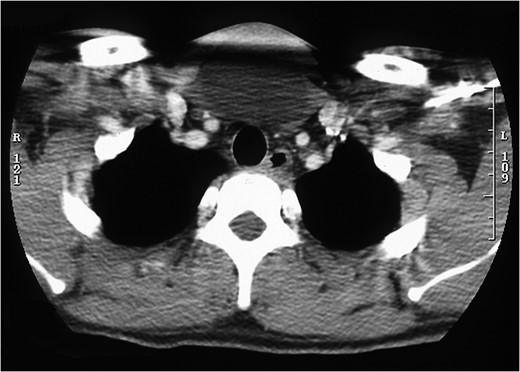

Cross-sectional image of midline neck lump with no tracheal communication.